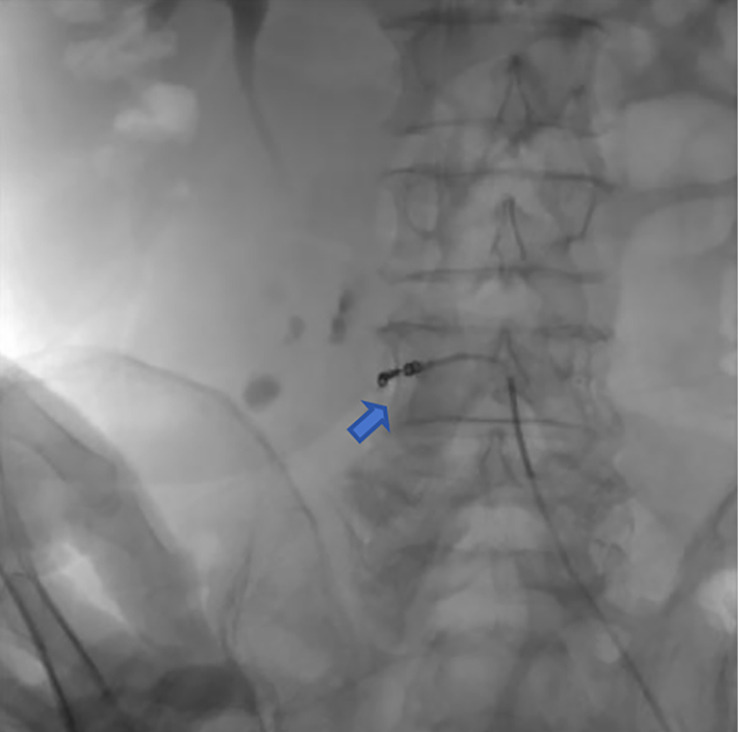

Transcatheter arterial embolization for retroperitoneal bleeding in patients with lumbar artery injury and essential thrombocythemia: a case description.